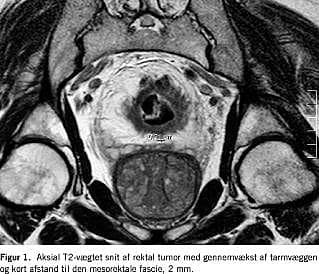

En MR-skanningsteknik med tynde T2-vægtede snit vinkelret på tumoren anvendes nu som standardteknik på mange institutioner ved stadieinddeling af cancer recti. MR med overfladespole eller endorektal spole giver mulighed for en nøjagtig bedømmelse af tumorens gennemvækst, men korrekt placering af endospolen er vanskelig. Perirektal stranding kan give anledning til over-stadieinddeling af T2-tumorer. T-stadie-inddelingen er endvidere afhængig af observatørerfaring [1]. Anvendelse af MR-kontraststof øger ikke nøjagtigheden af T-stadieinddelingen [2]. På de aksiale billeder ses den mesorektale fascie, hvorved afstanden fra tumoren til den meso-rektale fascie kan måles (Figur 1 ) [3]. Der er evidens for, at man med MR kan forudsige den circumferentielle resektionsmargin ved total mesorektal excision. Udmålingen af afstanden er ikke så observatørafhængig som T-stadieinddelingen. Ved T4-tumorer er MR bedre end TRUS til at påvise hele tumorens afgrænsning og mulige indvækst i naboorganer. Desuden er det muligt at fusionere MR med terapiskanning og indtegne strålefeltet. MR har ligesom ultralyd vist sig ikke at være optimal til påvisning af metastaser i de regionale lymfeknuder. En metaanalyse viste en sensitivitet på 66% [2]. Et dansk studie har også vist en høj sensitivitet [4]. Der er nye lymfeknudespecifikke MR-kontraststoffer under udvikling. MR synes ikke at være velegnet ved restadieinddeling efter præoperativ radiokemoterapi, pga. over-stadieinddeling både for T- og N-stadier.